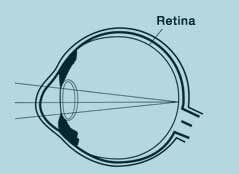

A healthy and good sight is based on clear images created on the retina.

The optical system of the eye is consisted of a cornea, lenses and vitreous directing the light beams we perceive as picture towards a direct focal point on the retina. This is usually the yellow spot and this directing is called refraction.

The light we perceive and spread by the objects first reaches the transparent surface on the eye called cornea; then the light is refracted by the lenses and it is focused on the retina in inner eye.

There, the light is perceived by the nerves inside the retina and it is transferred to the center of perception in the brain over the visual nerves. Here, these signals are converted into images.

Normal eye (Emmetropie)

When an emmetropic eye looks at a distance, light beams are connected on an accurate and clean image on the colour layer of the retina. This image scanned by our retina, consisted of innumerable spot sensor cells, is actually upside down, that is similar to a photo taken by a camera. Our brain processes the visual data received from both eyes and thus transforms it into a single and harmonies view of the image.

The structure of an eye is similar to that of a camera. Cornea functions like a lenses and it is a match for the front lenses of the camera objective. Pupil is like an amphibole of camera. And eye lenses are a match for other glass lenses in the camera objective. And finally, retina is like the film inside a camera.